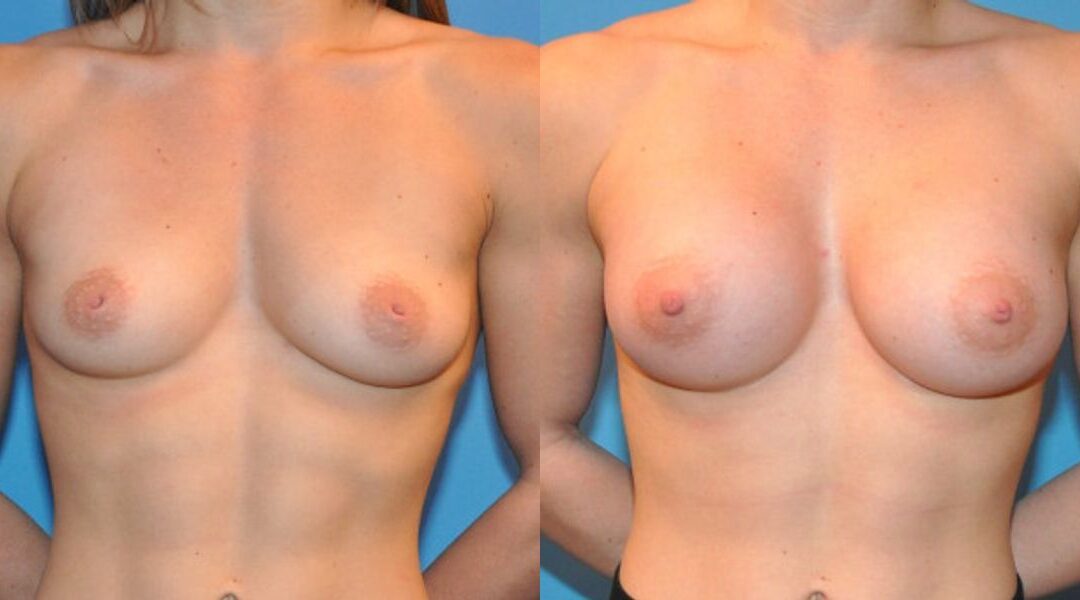

This 23 year old female dislikes the low profile appearnace of her breast shape. A 295 cc smooth round silicone implant was placed using a dual-plane technique. The result is a natural appearance along the upper pole of each breast and a rounder shape with more projection. She is delighted with her new look.